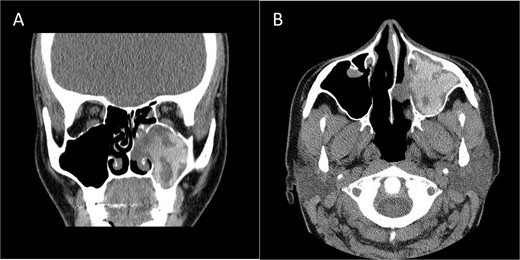

Coronal (A) and axial (B) CECT scan images showing left complete maxillary sinus heterogenous opacification.